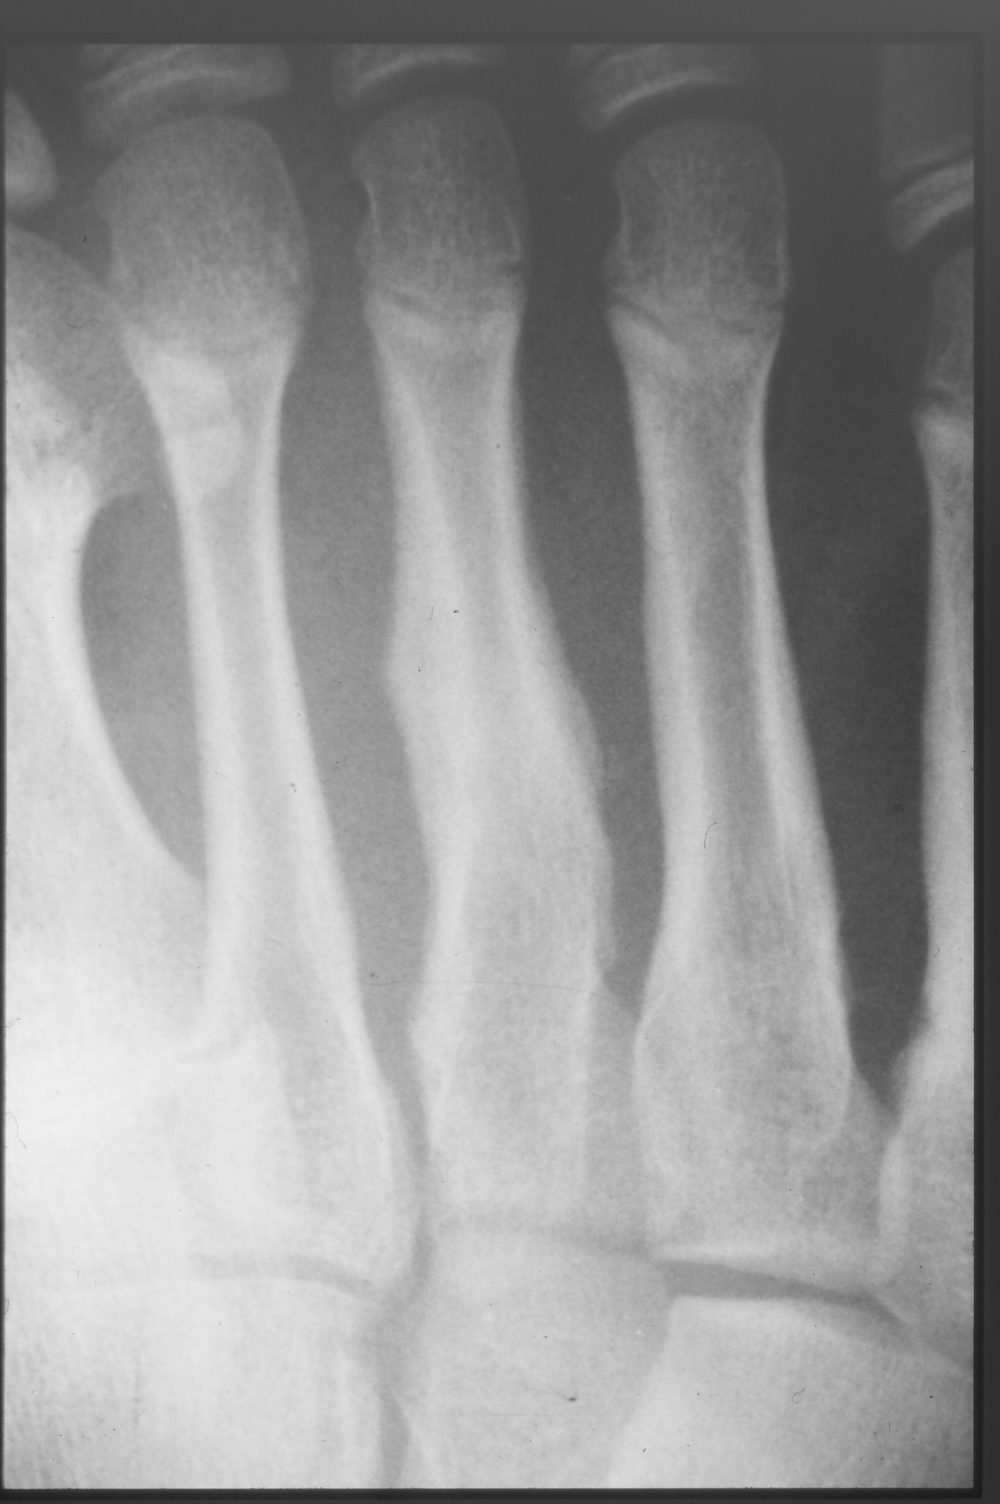

The symptom was relieved by rest from running for about 4 weeks. Play was gradually restarted from week 5, but complete recovery began at month 3. Bone formation was also good on X-ray at 3 weeks (Fig. 4) and 3 months (Fig. 5).

Figure 4 3 weeks after injury

Callus formation at the fracture site is accelerated at 3 weeks post-injury compared to initial presentation, but is still insufficient for resuming play.